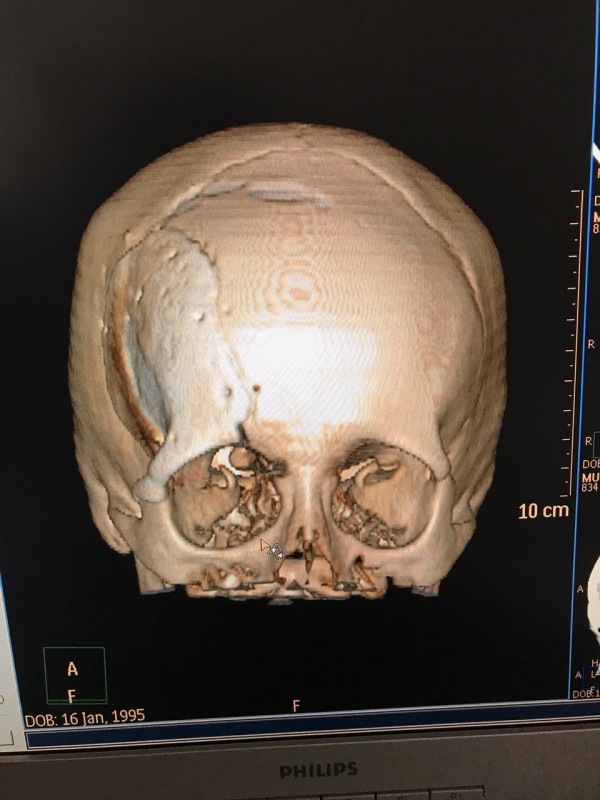

"Компьютерная томография показала, что костная опухоль поражала лобную кость и "крышу" орбиты глаза, которая, в свою очередь, сдавливала глазное яблоко. Чтобы убрать опухоль, потребовалось немало времени. Наша задача была сохранить глазное яблоко, зрительный нерв и сосуды. Если неправильно провести операцию и неправильно закрыть дефект, то в последующем это может привести к эстетической неполноте и асимметрии лица. Уникальность еще и в том, что в операции применялась 3D-стереолитография, которая делается только в Алматы", - рассказал он.

Снимок черепа. Опухоль с левой стороны. Фото предоставлено Константином Ли